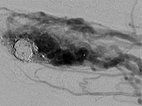

Nach Embolisation jetzt deutlich echoreiche Formationen mit dorsalem Schallschatten im Gefäß durch das Embolisat nach Auffüllen des AVM Nidus.